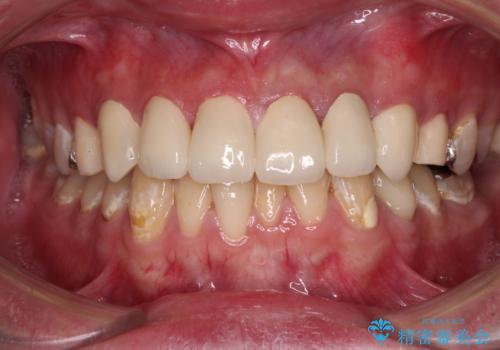

むし歯は多かったものの、歯肉の腫脹はそれほどなかったため、最小限の治療回数で治療を終えることができました。